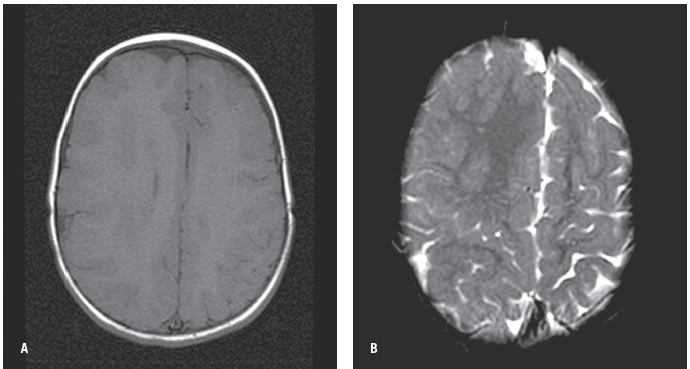

A 2-year-old girl with developmental delay, mental retardation, microcephaly, and seizures was born after a term pregnancy complicated by polyhydramnios (A). Shoulder dystocia occurred during delivery leading to left humeral fracture. Cleft lip and palate were noted at birth. The neonatal period was complicated by hypernatremia, which subsequently led to the diagnosis of diabetes insipidus, and she was started on desopressin. She was also noted to have core body temperature instability.

An MRI scan of the brain revealed semilobar holoprosencephaly. Abnormal and incomplete cleavage of the lobes was evident (B, C, and D). The anterior interhemispheric fissure was incompletely visualized on the scan; the posterior interhemispheric fissure was present. There was partial fusion of the basal ganglia and the thalami (E). An H-shaped monoventricle was noted.